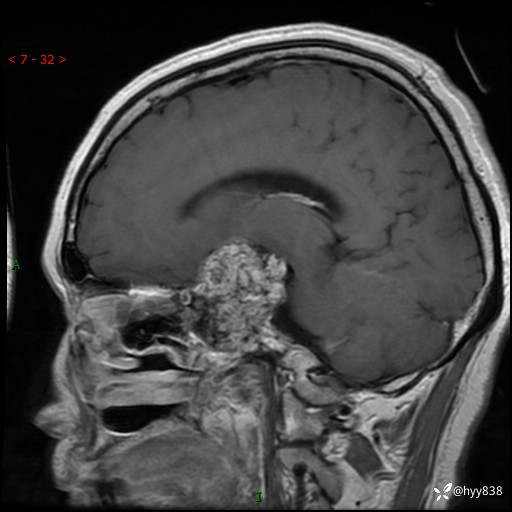

老年女性,视力下降3年。鞍区钙化性肿块,鉴别诊断有哪些---(有结果)

简要病史:患者3年前无明显诱因左眼出现视力下降,出现视物模糊,无头痛,无头晕,无恶心、呕吐,无意识障碍,无肢体麻木及抽搐,无心慌、胸闷,无腹痛、腹胀等不适,无旋地转感。个月前右眼视力下降,患者视物模糊逐渐下降,自诉看东西有雾感。在当地医院眼科就诊,症状无好转,行头部MR提示:鞍区肿物。现患者为求诊治来我科就诊,在当地市中医医院行头部CT:提示鞍区占位。患者现求进一步诊治来我院就诊,门诊以“鞍区肿物”收入我科。 患病以来,患者精神、饮食、睡眠尚欠佳,大小便如常,体力体重无明显变化。

临床诊断:鞍区肿物

鞍区MRI平扫

增强 COR +SAG